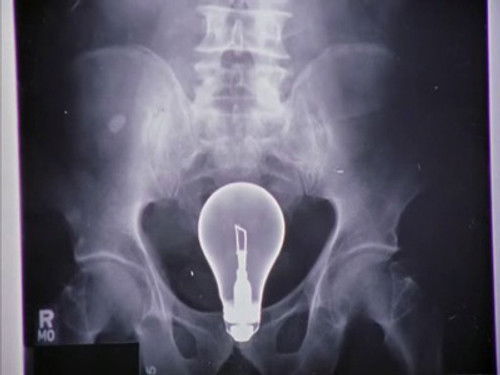

Доктор Кокс назначает Джей Ди и Эллиот руководителями резидентуры, однако из-за проблем во взаимоотношениях им тяжело работать вместе. Кокс и Тёрк озадачены проблемой извлечения большой лампочки из ануса пациента и вынуждены прибегнуть к помощи Уборщика.